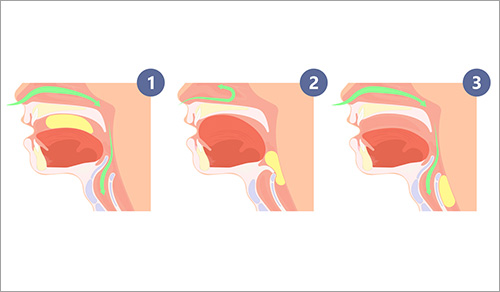

From novel minimally invasive approaches in head and neck surgery for benign and malignant tumors to programs dedicated to voice preservation and recovery, restoring hearing, and managing sleep disorders, our otolaryngologists and laryngologists from Columbia and Weill Cornell Medicine offer patients diagnostic and therapeutic procedures that optimize functional and aesthetic outcomes.

Otolaryngology (ENT)